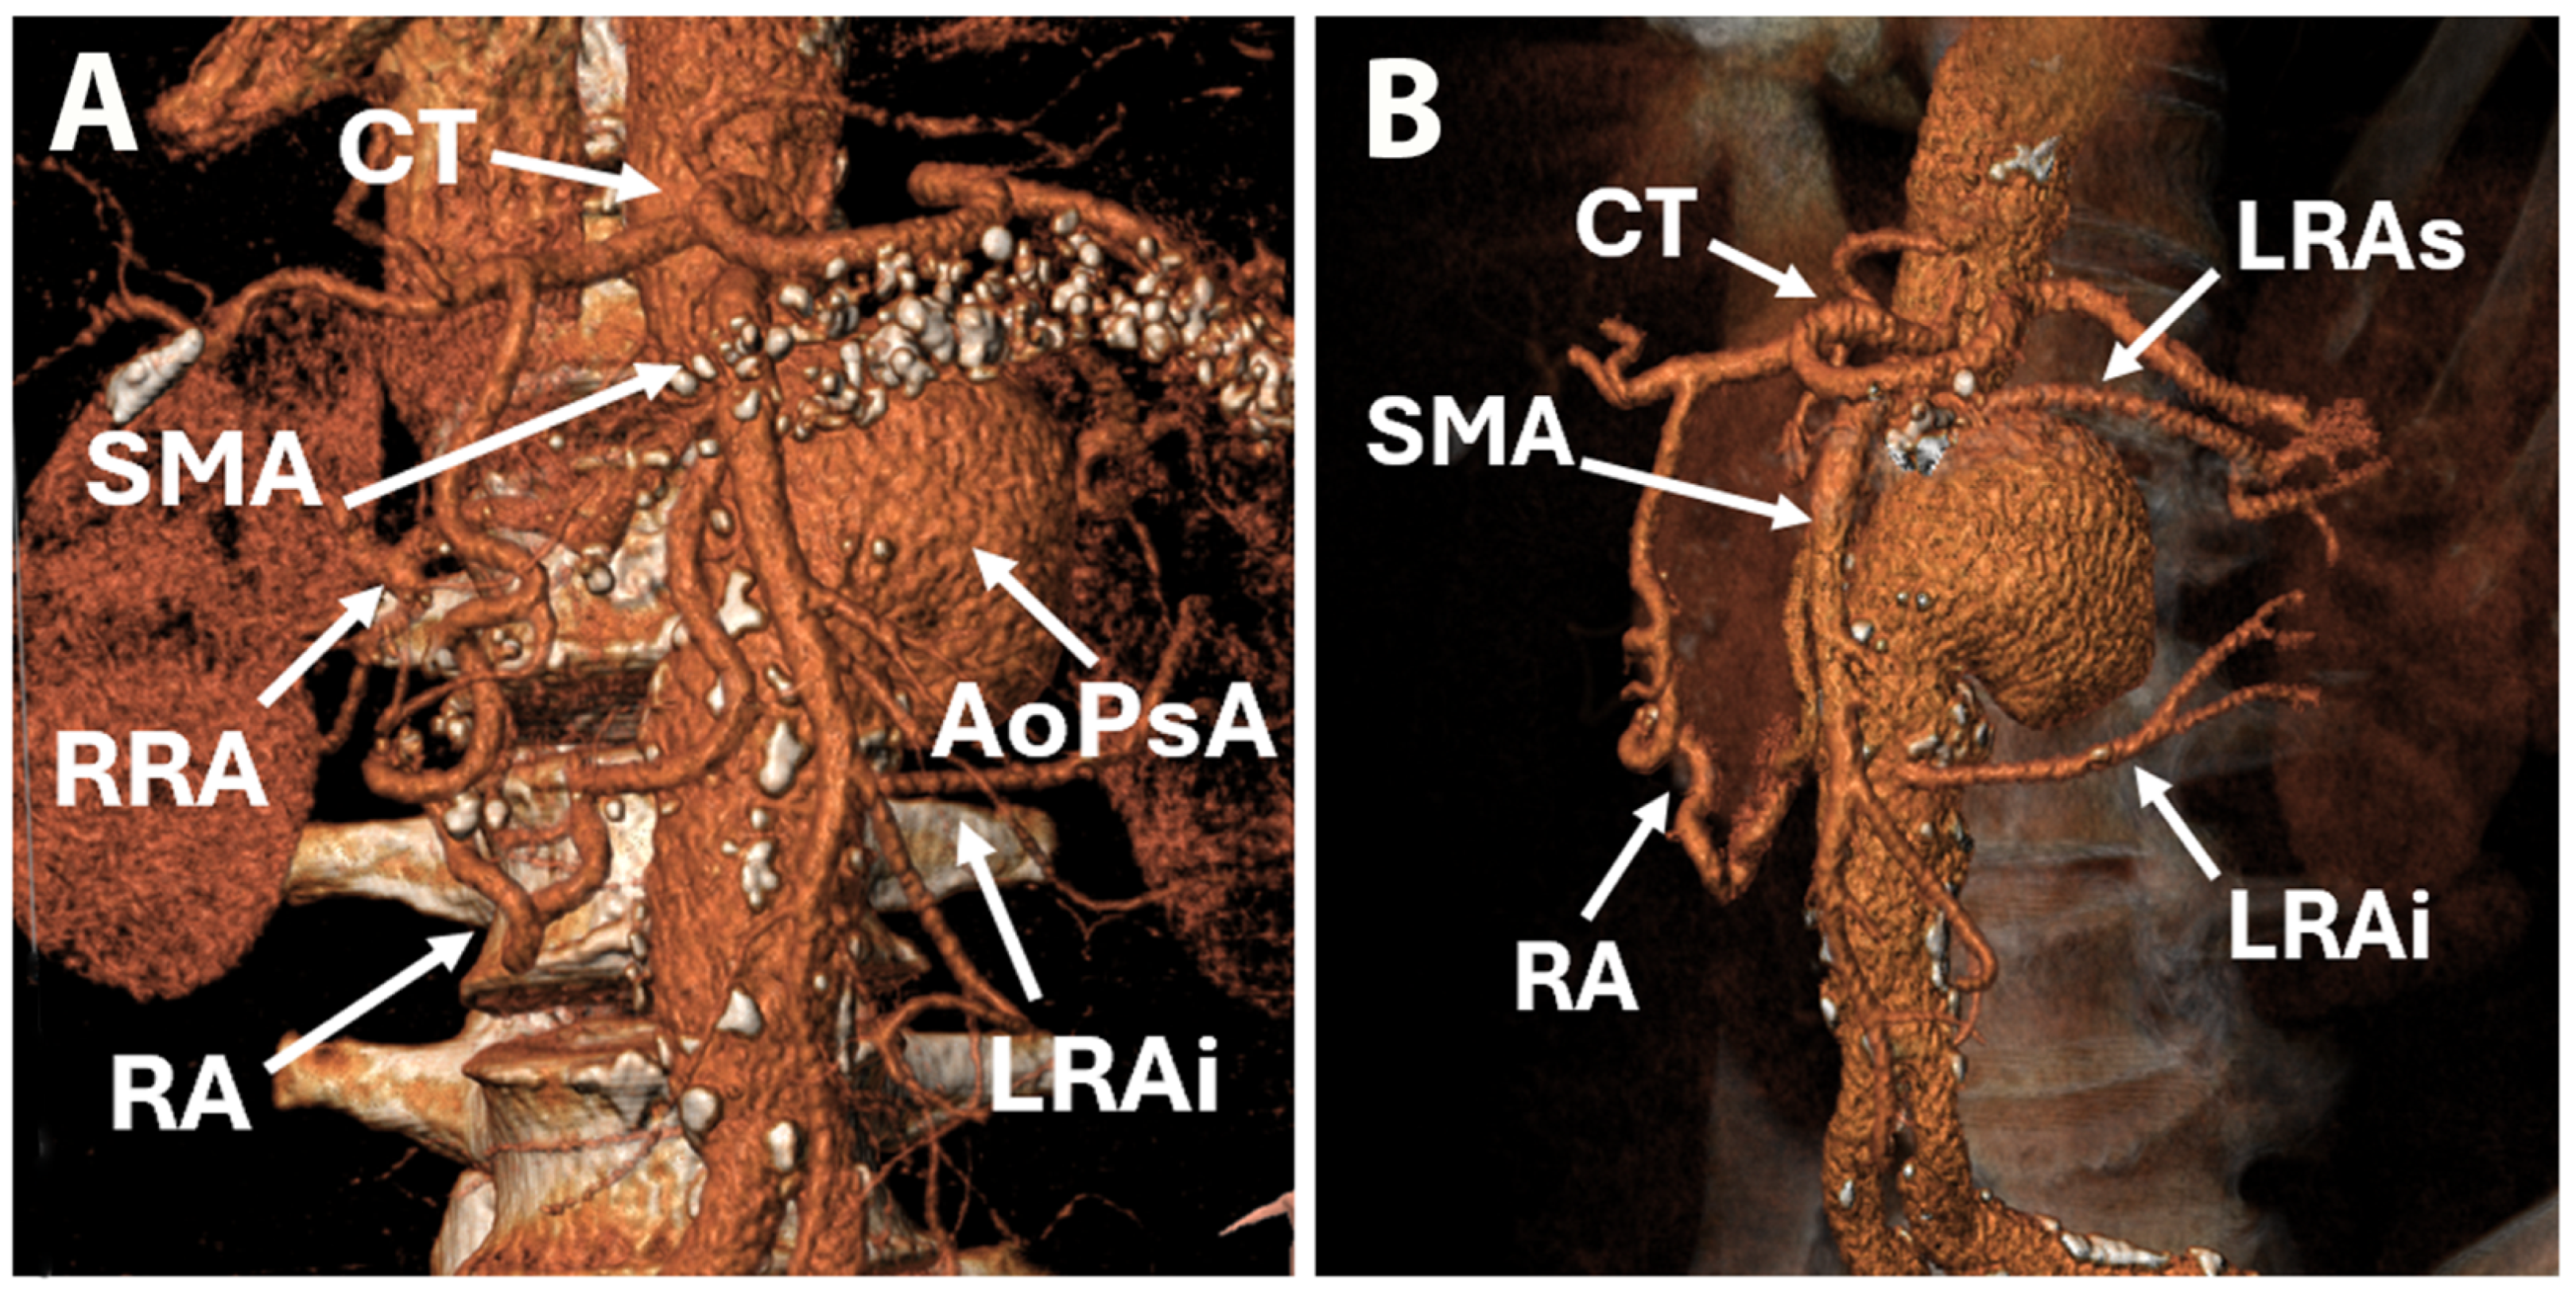

2. Case Report